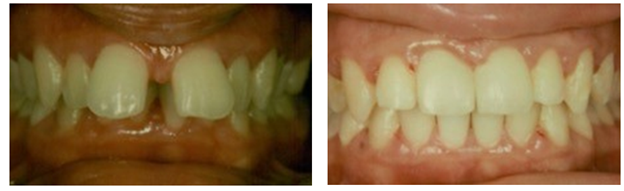

Figure 5 A&B Pretreatment of mild cupping / alveolar bone deficiency of the maxillary right premolars (arrow) and severe cupping of the maxillary maxillary right lateral incisor (arrow).

Figure 5 C&D Post treatment of mild cupping / alveolar bone deficiency of the maxillary right premolars and severe cupping of the maxillary right lateral incisor.